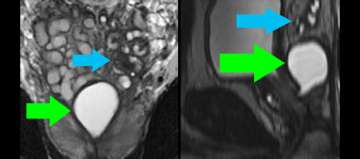

8) Benign Disease (Infertility)

Benign Disease (Infertility)

• Young man presents with infertility (azospermia)

• Workup and medical history otherwise noncontributory

• Muellerian duct remnant in central upper prostate may obstruct ejaculatory ducts

• Left seminal vesicles are atrophic

• Read More >